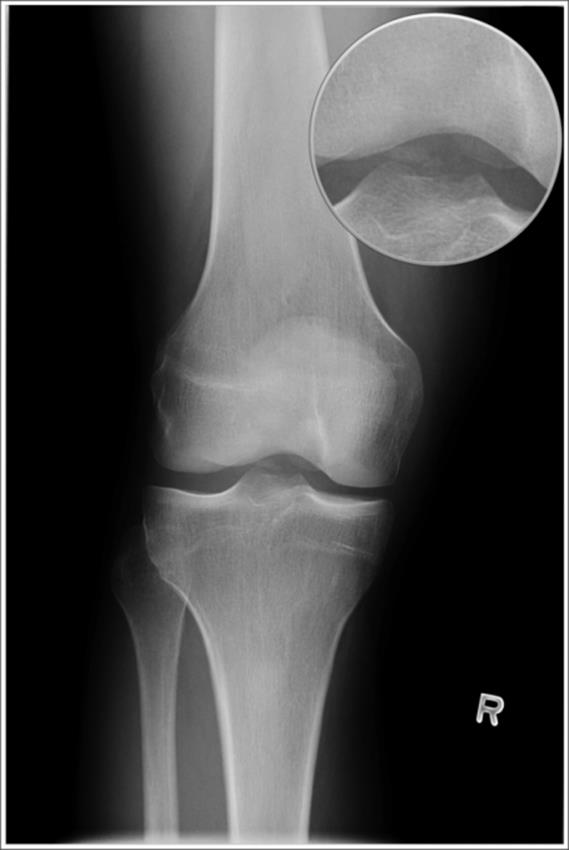

o Segond fracture (see Figure 4.8) – a vertically oriented avulsion fracture off the lateral tibial condyle – low sensitivity (

5%), but high specificity (75–100%), so not often seen with ACL injuries, but if it is seen, then the patient likely has suffered an ACL tear

Figure 4.7 Avulsion of the tibial spine. An uncommon radiograph finding for an adult with an ACL tear. This finding is more typically seen in children who suffer ACL tears. Fracture is highlighted by the arrow. Inset shows fracture magnified. (Image courtesy of Arun Sayal, MD.)